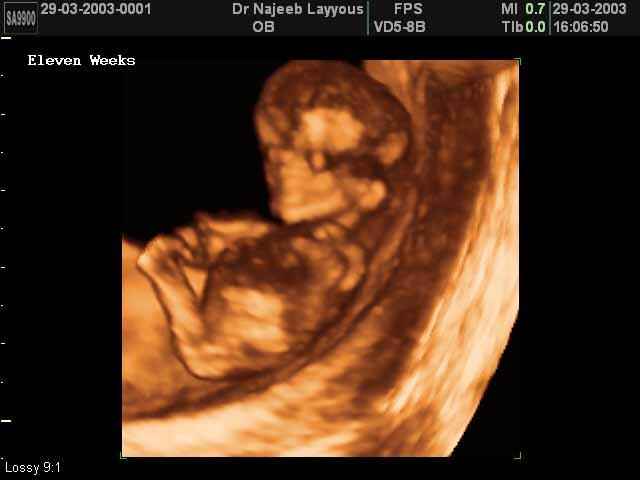

3D First Trimester Ultrasound Scan Photos